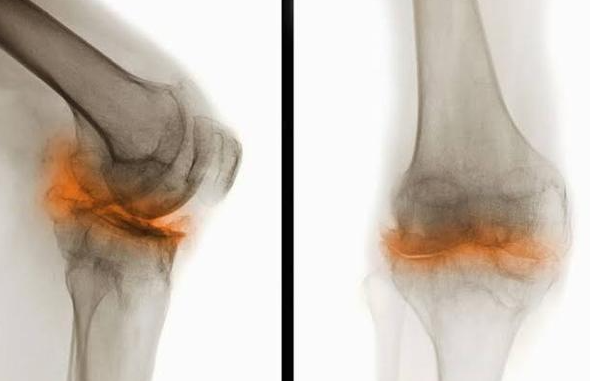

This grinding sensation, known as crepitus, can be a sign of:

- Cartilage Softening (Chondromalacia):The cartilage on the underside of the kneecap becomes soft and frayed, like a piece of carpet backing that’s starting to shred.

- Osteoarthritis:This is the “wear-and-tear” arthritis many of us have heard about. The smooth cartilage cushion continues to thin and erode. In advanced stages, it can wear away completely, leading to a “bone-on-bone” grinding sensation. The sound you’re hearing is the rough, irregular surfaces of the bones rubbing against each other without their protective cushion.